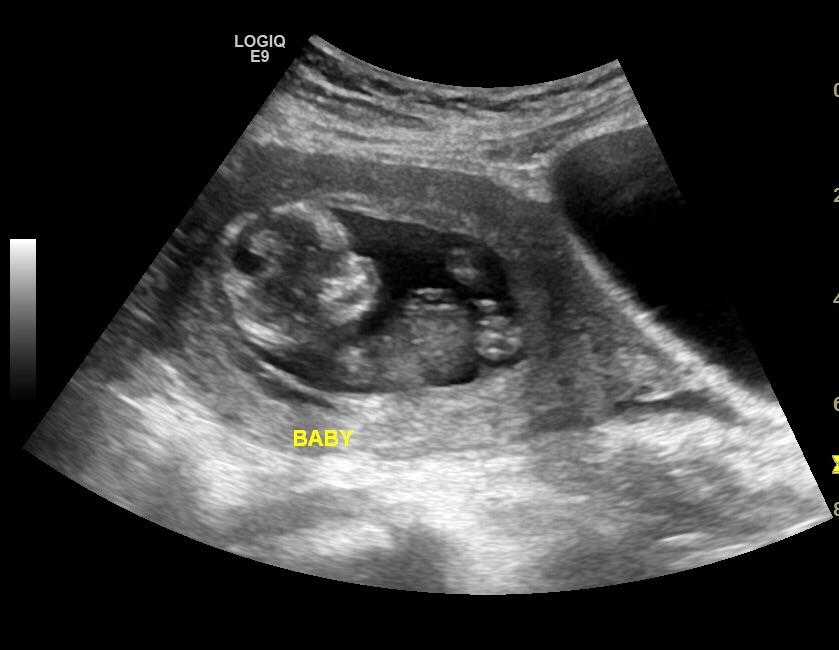

We have 3 girls and have a feeling this is probably another little princess. 😁 :DD:Thank you for your guesses!

It's a bit blurry but kind of looks boyish to me!

That top picture looks all boy to me...

Thinking boy, too! How far along was the scan taken at?

Eek! Maybe! It was taken yesterday at 12 weeks 4 days. :)

Could you post a bigger version of your top pic? I find it hard to see, it's so small :) Looks like maybe a boy potty.

Yay! Scan was at 12 weeks, 4 days!

Looks boyish.

I'm new at this but my first thought was boy.

BOY

I would guess boy too :) good luck keep us updated !!

Looks pretty boyish to me!!!

All boy!